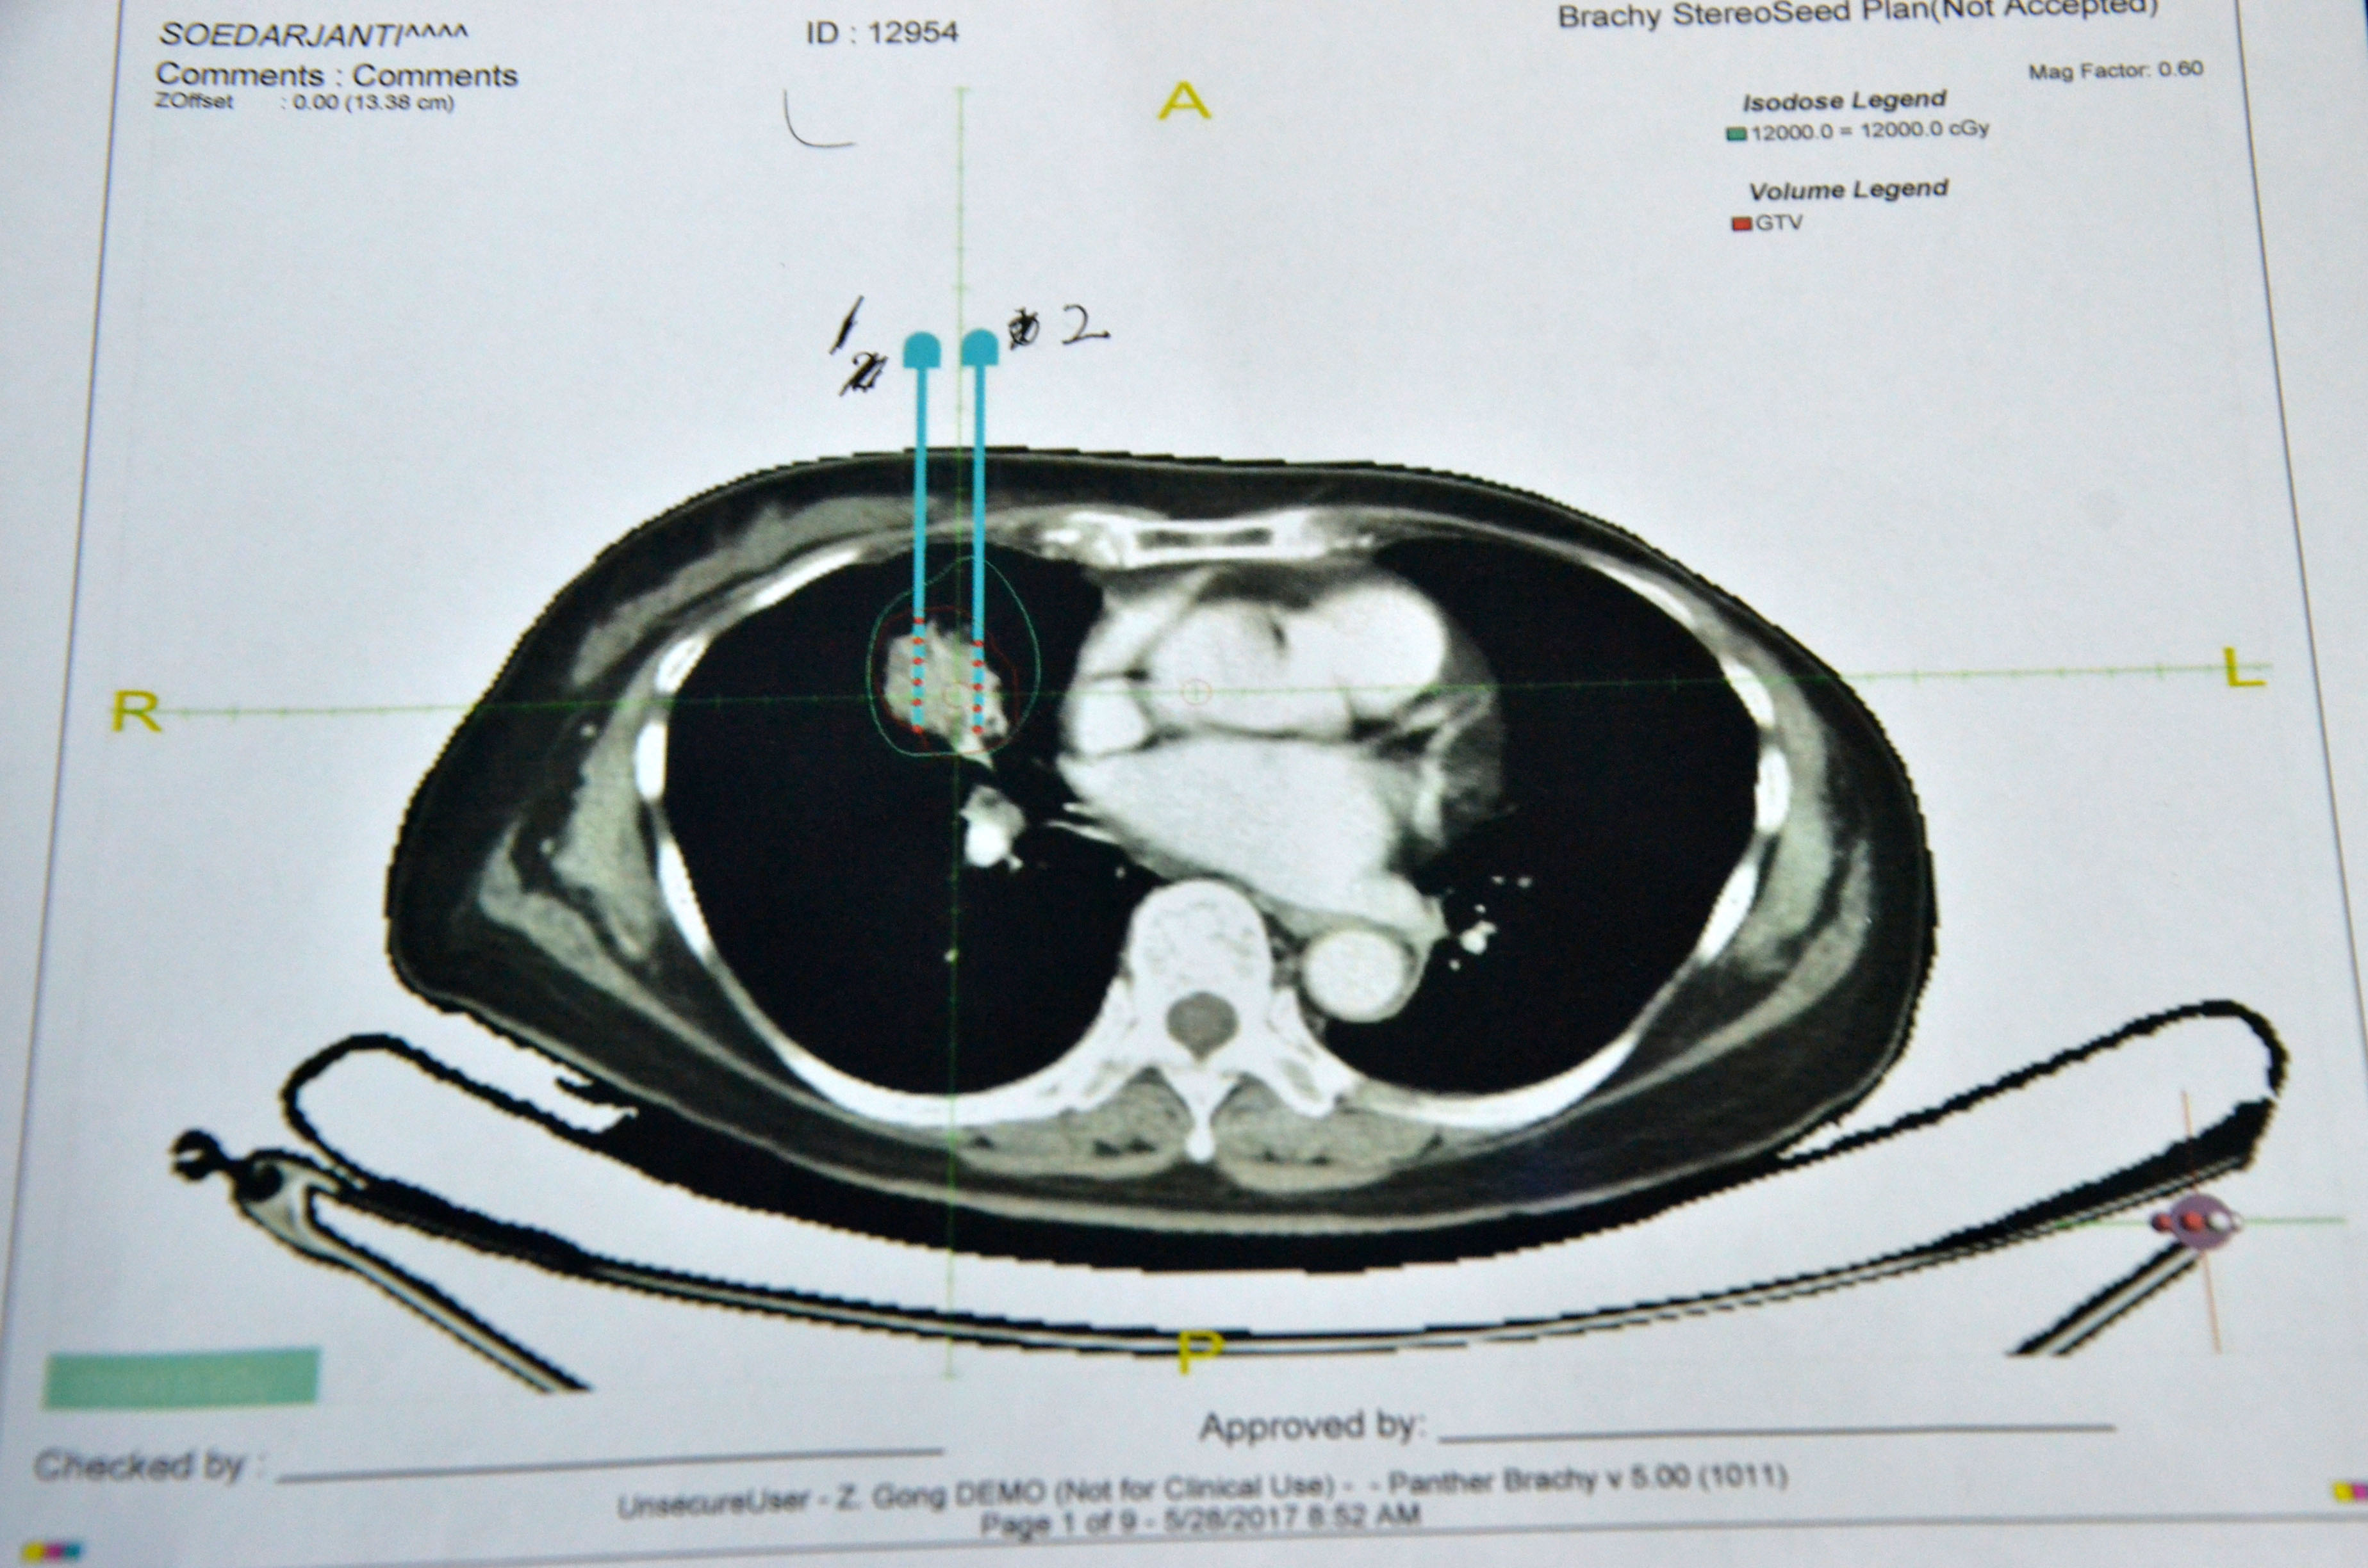

▲术前计划

术前患者进行了CT检查,利用CT进行3D建模,通过PROWESS TPS软件(粒子植入治疗计划系统)将患者肿瘤CT扫描图像进行三维重建,完整地呈现出患者皮肤、骨骼、血管和肿瘤之间的关系。设计出每一根穿刺针的进针路径、进针深度、粒子分布及粒子数量、肿瘤受辐射的剂量,最后通过3D打印设备制作出贴合患者皮肤的3D微创导向模板。